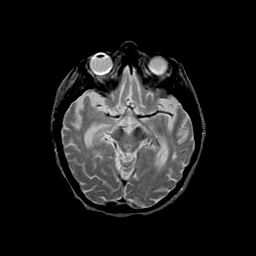

Basal Ganglia Calcification: T2-weighted MR -- Slice #7

[Home][Help][Clinical] Slice 7